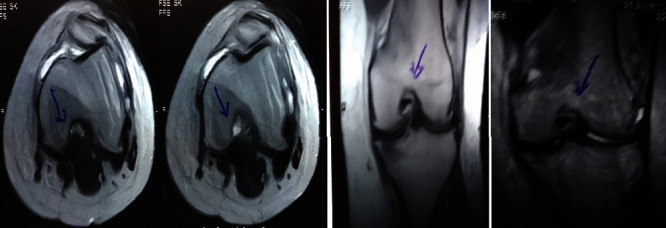

治療后一個(gè)月進(jìn)行隨訪(fǎng)。在第一次細胞治療后,患者的疼痛明顯減輕。第二次療程后,她沒(méi)有疼痛,并注意到運動(dòng)范圍有所改善。持續的物理治療也觀(guān)察到下肢肌肉力量的增加。從治療開(kāi)始(11個(gè)月前)到最后一次隨訪(fǎng)(4個(gè)月前),患者按照建議的飲食和基于運動(dòng)的方案減重了11公斤。因此,她現在整體身體健康,能夠更舒適地進(jìn)行日常生活活動(dòng)。表3顯示治療前后的MRI檢查結果。人物的圖1和的和圖2顯示半月板撕裂的治療前和治療后(1年后)圖片。觀(guān)察到損傷程度的改善圖2。

圖1:治療前MRI顯示內側和外側半月板后角的III級撕裂。